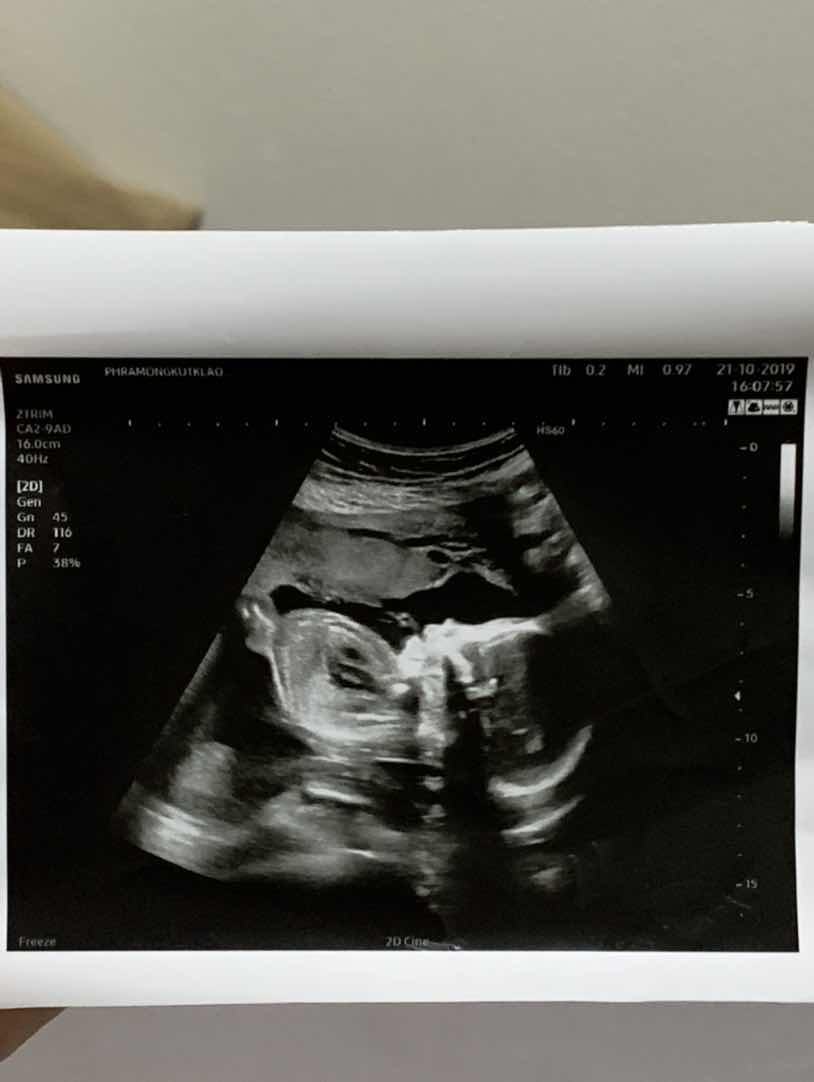

ตอน15weekค่ะ มุมเดียวกันเลย

กำลังจะเข้า5เดือนค่ะ

4เดือนครึ่งค่ะ ผชค่ะ